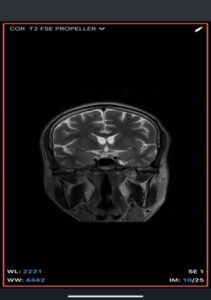

Imaging Findings-

- MRI

- T1-weighted: Hyperintense (fat signal).

- T2-weighted: Variable, usually hyperintense; may show chemical shift artifacts.

- Fat-suppressed sequences: Complete signal suppression confirms fat composition.

- Post-contrast: No enhancement.

- Often associated with:

- Corpus callosum agenesis/dysgenesis

- Interhemispheric cysts